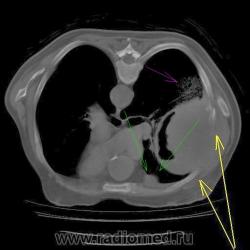

Вопрос 1.

Понятно, что сиреневой стрелкой обозначен "парапроцесс". А вот, что обозначено зелеными стрелками? Для меня это вопрос.

Dr.Mario, как Вы думаете, "природа" образования и участка, обозначенного Валентином Львовичем зелеными стрелками, одна? Если да, то тогда выходит, что "субстрат" здесь уже не нужен?